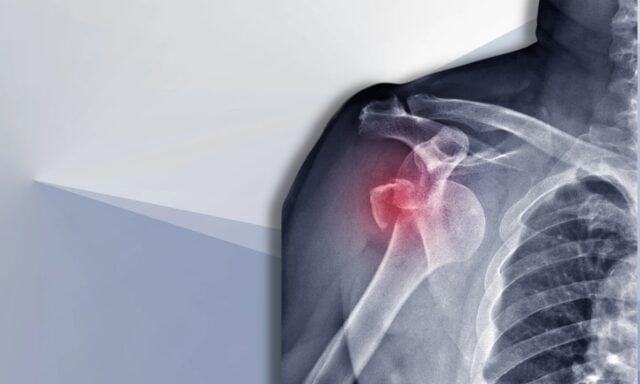

سنتحدث في هذه الحلقة عن كل ما يتعلق بعدم استقرار الكتف. ستتعرف على المزيد حول تصنيف ستانمور والضرر الهيكلي بعد الخلع. سنناقش المريض النموذجي الذي يعاني من عدم ثبات الكتف وكيف تبدو عملية الفحص. سوف نتطرق إلى أنماط تنشيط العضلات والجراحة وكيف يمكن أن تبدو المعالجة الفيزيائية العلاجية لمريض يعاني من عدم استقرار الكتف. لذا احرص على الاستماع إلى الحلقة كاملة!